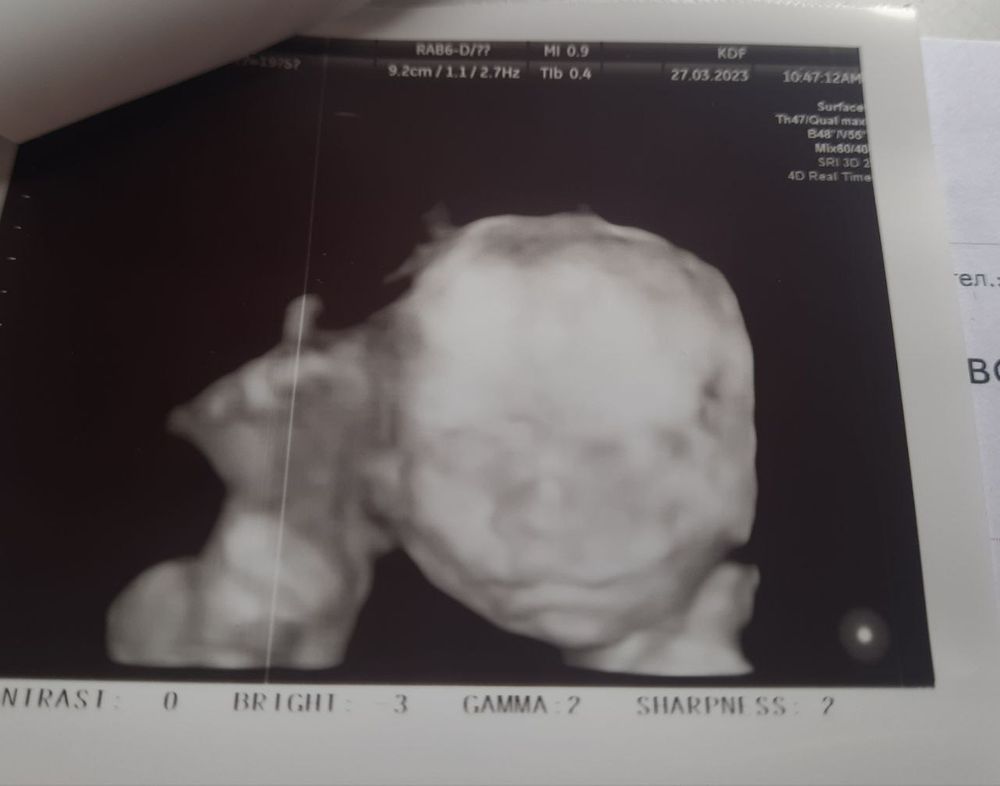

Ну и фоточки, сегодня даже 3д сделали нам)

а мне 3д понравились, они обе на папу похожи, носики аккуратненькие, ножки длинные, красотки) хотя я на всех детей так умиляюсь теперь)))

Ирина Р, нет, у нас обычный скрининг был, 3д просто включали, чтобы губки посмотреть, глазки и тд, и вот у второй дочки еще позвоночник никак схватить не могли, только 3д помогло) а так-то обычные черно-белые фотки в 2д) я думаю, потом наглядимся еще, когда встретимся, до 3х недель будут те еще красотульки сморщенные)))